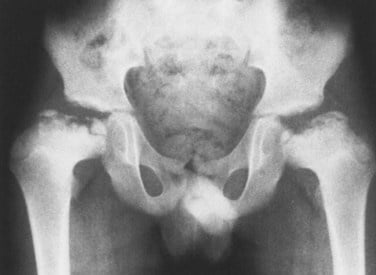

Dr. Pradeep Kumar, with expertise in joint replacement and musculoskeletal oncology extended to pediatrics, manages common conditions like clubfoot (Ponseti casting), developmental dysplasia of the hip (Pavlik harness), scoliosis (bracing or fusion), limb length discrepancies (epiphysiodesis or lengthening), cerebral palsy gait abnormalities, and pediatric fractures/tumors.